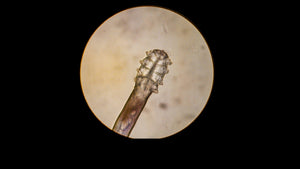

Your Friendly Eyelid Mites!

You can’t see them, but they’re there. They are microscopic mites, eight-legged creatures more like spiders. Almost every human being has them. They spend their entire lives on our faces, where they eat, mate and, finally die.

It looks as if there is something special on our faces that they need. Researchers are still looking to find their diet secrets. They are not harmful to us but they are linked to skin conditions like rosacea.

Studies have found that people suffering from rosacea tend to have more Demodex mites. Instead of 1 or 2 per square centimeter of skin, the number rises to 10 to 20. There may also be a link with the immune system, which normally protects us against infections. When Demodex mites die, their bodies leave waste and bacteria which cause irritation and inflammation.